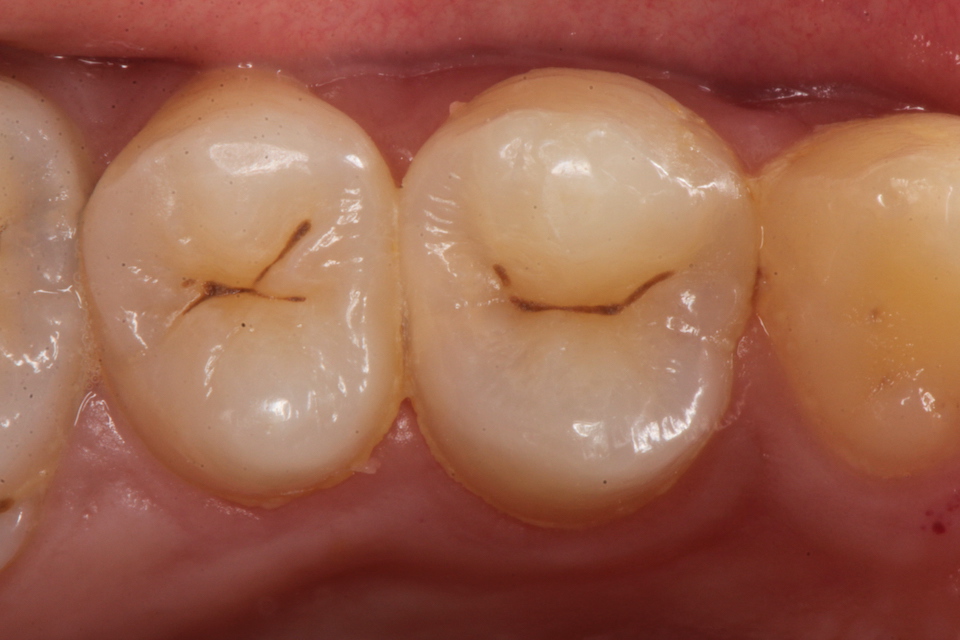

下顎7番の頬側歯茎部カリエスの原因 2025.06.04